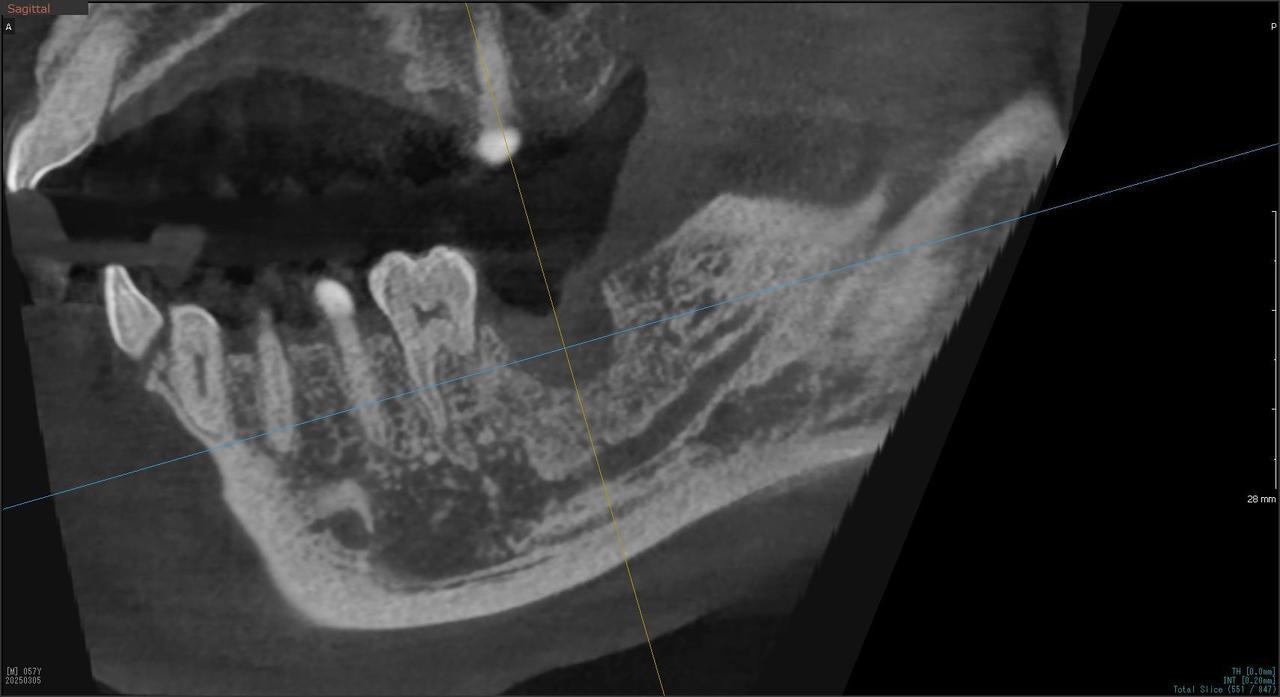

5.左上4番のインプラント抜歯即時埋入、左上6番の上顎既存骨1から2mmのグラフトレスサイナスリフト、左下56の大幅な骨欠損により、下顎神経の損傷を回避するために、ショートインプラントを使用し、左下56にインプラントを埋入し、最終補綴物は、左上456の3ユニットのジルコニアブリッジし、左下56は、ジルコニアの連結冠を装着したケース

Before

枚方市のインプラントの症例

M・I 様 女性 70代

症状としては、左下56は、歯周病で欠損したと考えられるが、かなりの骨欠損をともなっていた。左上456に関しては、動揺が大きく、炎症が起き、排膿、および、歯性上顎洞炎を起こしていた。

治療法としては、動揺がひどくなってきて、炎症の症状もあったため、左上56の抜歯を希望。インプラント治療をその後、希望したため、左上4に関しては抜歯即時埋入。左上6に関しては、既存骨1から2mmでインプラント治療が厳しい状態であったが、グラフトレスサイナスリフトを行い、治療期間5か月はかかるということを説明して、インプラント埋入をおこないました。その後、2か月半後、大幅に骨が欠損している下顎56に対して、ショートインプラントを使用して、下顎神経の損傷を避けて、インプラント埋入を終えています。その後2か月後に光学印象で印象を行い、上顎刺億456歯、3ユニットのジルコニアブリッジを装着。下顎左側56に関しては、骨欠損が大きいため、歯冠長がだいぶ長くなるため、ジルコニアの連結冠を装着して治療を終えた。

治療結果は、上顎6に関しては、既存骨が少なく、厳しい治療ではありましたが、5か月で治療を終え、患者様の負担を最小限に抑えるができたと考えます。(従来のサイナスリフトでは、このようなケースでは1年以上、1年程度の治療期間がかかるか、治療が不可能と言われるケースだと考えます。)また、下顎は骨欠損が大きく、下歯槽管のリスクが起きることが考えられますが、ショートインプラントを使用することで安全に治療を行うことができました。

治療の期間・回数:治療期間5か月(上顎456 3ピースブリッジの治療は5か月(上顎既存骨が2mm程度しかなく、骨結合に時間がかかるケースであったために、5か月の治療期間が必要であった。)(左下56に関しては2か月半で治療を終えています。)治療回数は、13回。

治療の価格:1,474,000円(税込)

治療費の内訳:左上46および左下56のインプラント基本料(フィックスチャー及び手術費用、投薬費用、レントゲン費用、インプラント上部費用(アバットメントおよびジルコニアクラウンの費用用)330000円(税込み)×4本分 1320000円(税込)。左上5ジルコニアポンテック費用88000円(税込)。オプション費用、左上4抜歯即時埋入加算(人工骨費用を含む)+グラフトレスサイナスリフト費用 33000円(税込)、左上6グラフトレスサイナスリフト費用 33000円(税込)